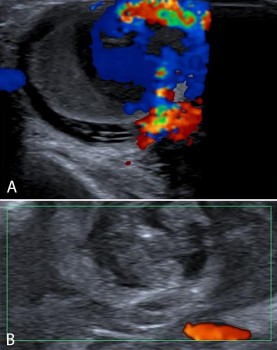

Op de echo wordt ter plaatse van de zwelling een vaatstructuur van > 2 cm gezien met een pulserende flow [figuur 3]. Er wordt direct een CT-angiogram gemaakt, waarop tegen de a. radialis een bolvormige laesie met een diameter van 3 cm te zien is [figuur 4]. De laesie kleurt volledig aan, passend bij een aneurysma spurium. In verband met de pijnklachten wordt mevrouw De Greef verwezen naar de Spoedeisende Hulp. Aldaar wordt de antistolling stopgezet in de verwachting dat de zwelling zal stollen en het stolsel langzaam zal worden opgeruimd. Op de controle-echo’s na 2 weken blijkt echter nog steeds flow aanwezig. Hierop krijgt mevrouw De Greef een trombine-injectie toegediend in de zwelling. Na 6 weken is vrijwel het gehele aneurysma geresorbeerd. Vermoedelijk was het ontstaan ten gevolge van de hartkatheterisatie enige maanden geleden.

Figuur 3 | Echografie van een aneurysma spurium. Voor behandeling is de flow duidelijk zichtbaar (a), na het staken van antistolling wordt bijna geen flow meer gezien (b)